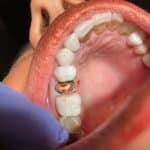

- Kanal tedavisi nedeniyle kırılgan hale gelen dişlerin korunmasında,